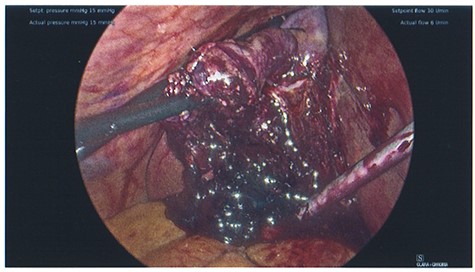

The patient was taken to theatre the second day of the admission. At laparoscopy, the gallbladder was visibly necrotic. The gallbladder was inadvertently perforated during retraction and a large volume haematoma was evacuated, as shown in Fig. 4. Dissection proceeded normally and the critical view was achieved. No intraoperative cholangiogram was performed due to the inflamed and friable nature of Calot’s triangle. The cystic duct and artery were clipped and cut, allowing the gallbladder to be dissected off the cystic plate. Surgicell was placed in the gallbladder fossa and a 15fr drain was secured. The drain was subsequently removed the day following operation, and on Day 2, the patient was discharged on a normal diet, having restarted apixaban.

Photo taken intraoperatively, demonstrating haematoma leaking from a necrotic gallbladder.